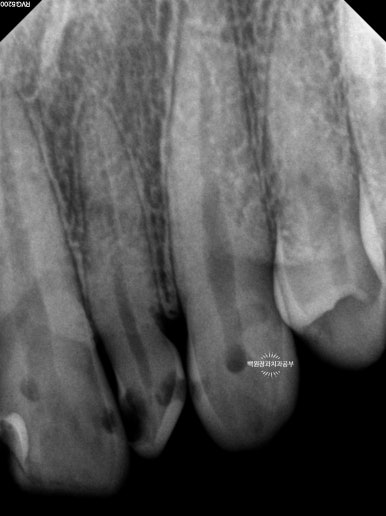

얼마나 충치가 진행되었는지 눈으로만 확인하지 않습니다.

치근단 사진을 촬영하여 보다 자세히 살펴볼 수 있었습니다.

눈으로 보는 것과 같은 위치입니다만, 엑스레이로 보았을 때 현재 위치하는 충치가 치아 내부의 신경관과 얼마나 가까이 위치하는지를 확인할 수 있었습니다.

이에 가장 충치가 심했던 측절치는 신경치료를 할 가능성이 아주 높으며 기둥을 설치해야 한다는 정보를 얻을 수 있었습니다.

신경치료가 완료되면 해당 치아속의 재료는 방사선 사진 상 하얗게 표시되게 됩니다.

신경치료 완료 후 남은 치아가 너무 적은 경우에는 치아 내부에 기둥 (=포스트)를 설치하게 됩니다.

눈에 보이는 부분의 치아가 너무 적으니 내부에서라도 힘을 얻으려는 노력이지요.